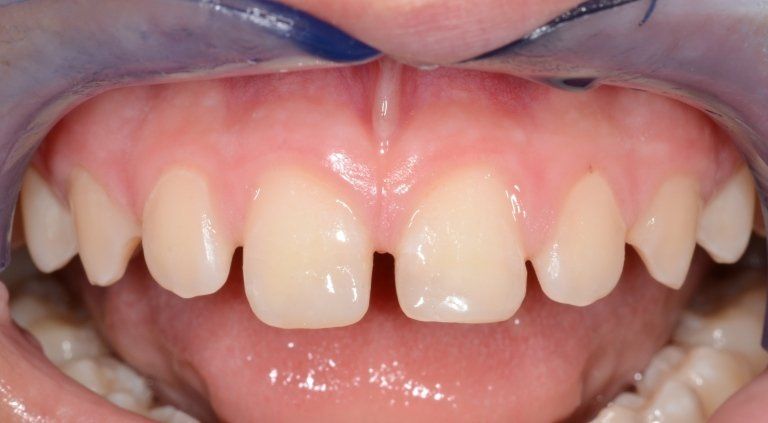

La frattura degli incisivi permanenti in un giovane paziente. I denti verranno ricostruiti in maniera diretta, alla poltrona.

Il caso può essere visionato in maniera più estesa nella sezione "traumi dentari" delle Prestazioni Bambini.